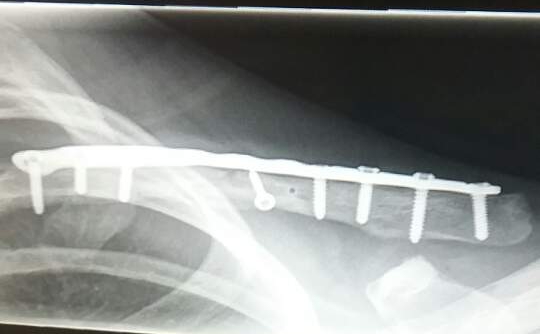

I am a 13 year old soccer goalkeeper on a U.S. Soccer Development Academy team. During a practice I broke my collarbone in 2 places. Unfortunately the break was more complicated than initially thought and I required surgery. I had never had any type of injury before and was pretty scared. And I really do not like hospitals. Dr. Dines made me feel very safe and told me I would be back on the field 3 to 4 months later full strength. The experience was very smooth and I actually was able to go home the same day. And just like he said I was back in goal good as new 4 months later. Thank you Dr. Dines!!